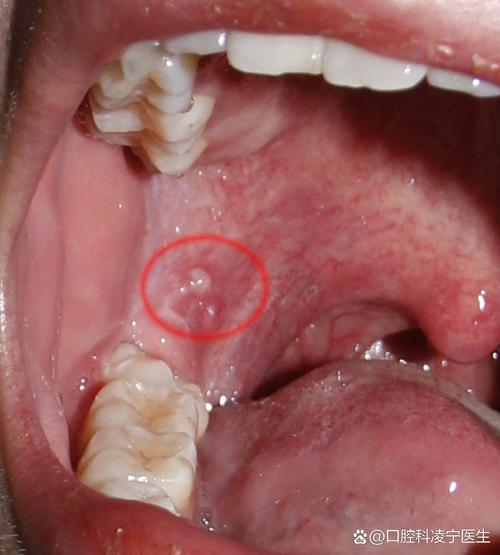

(图片来源网络,侵删)